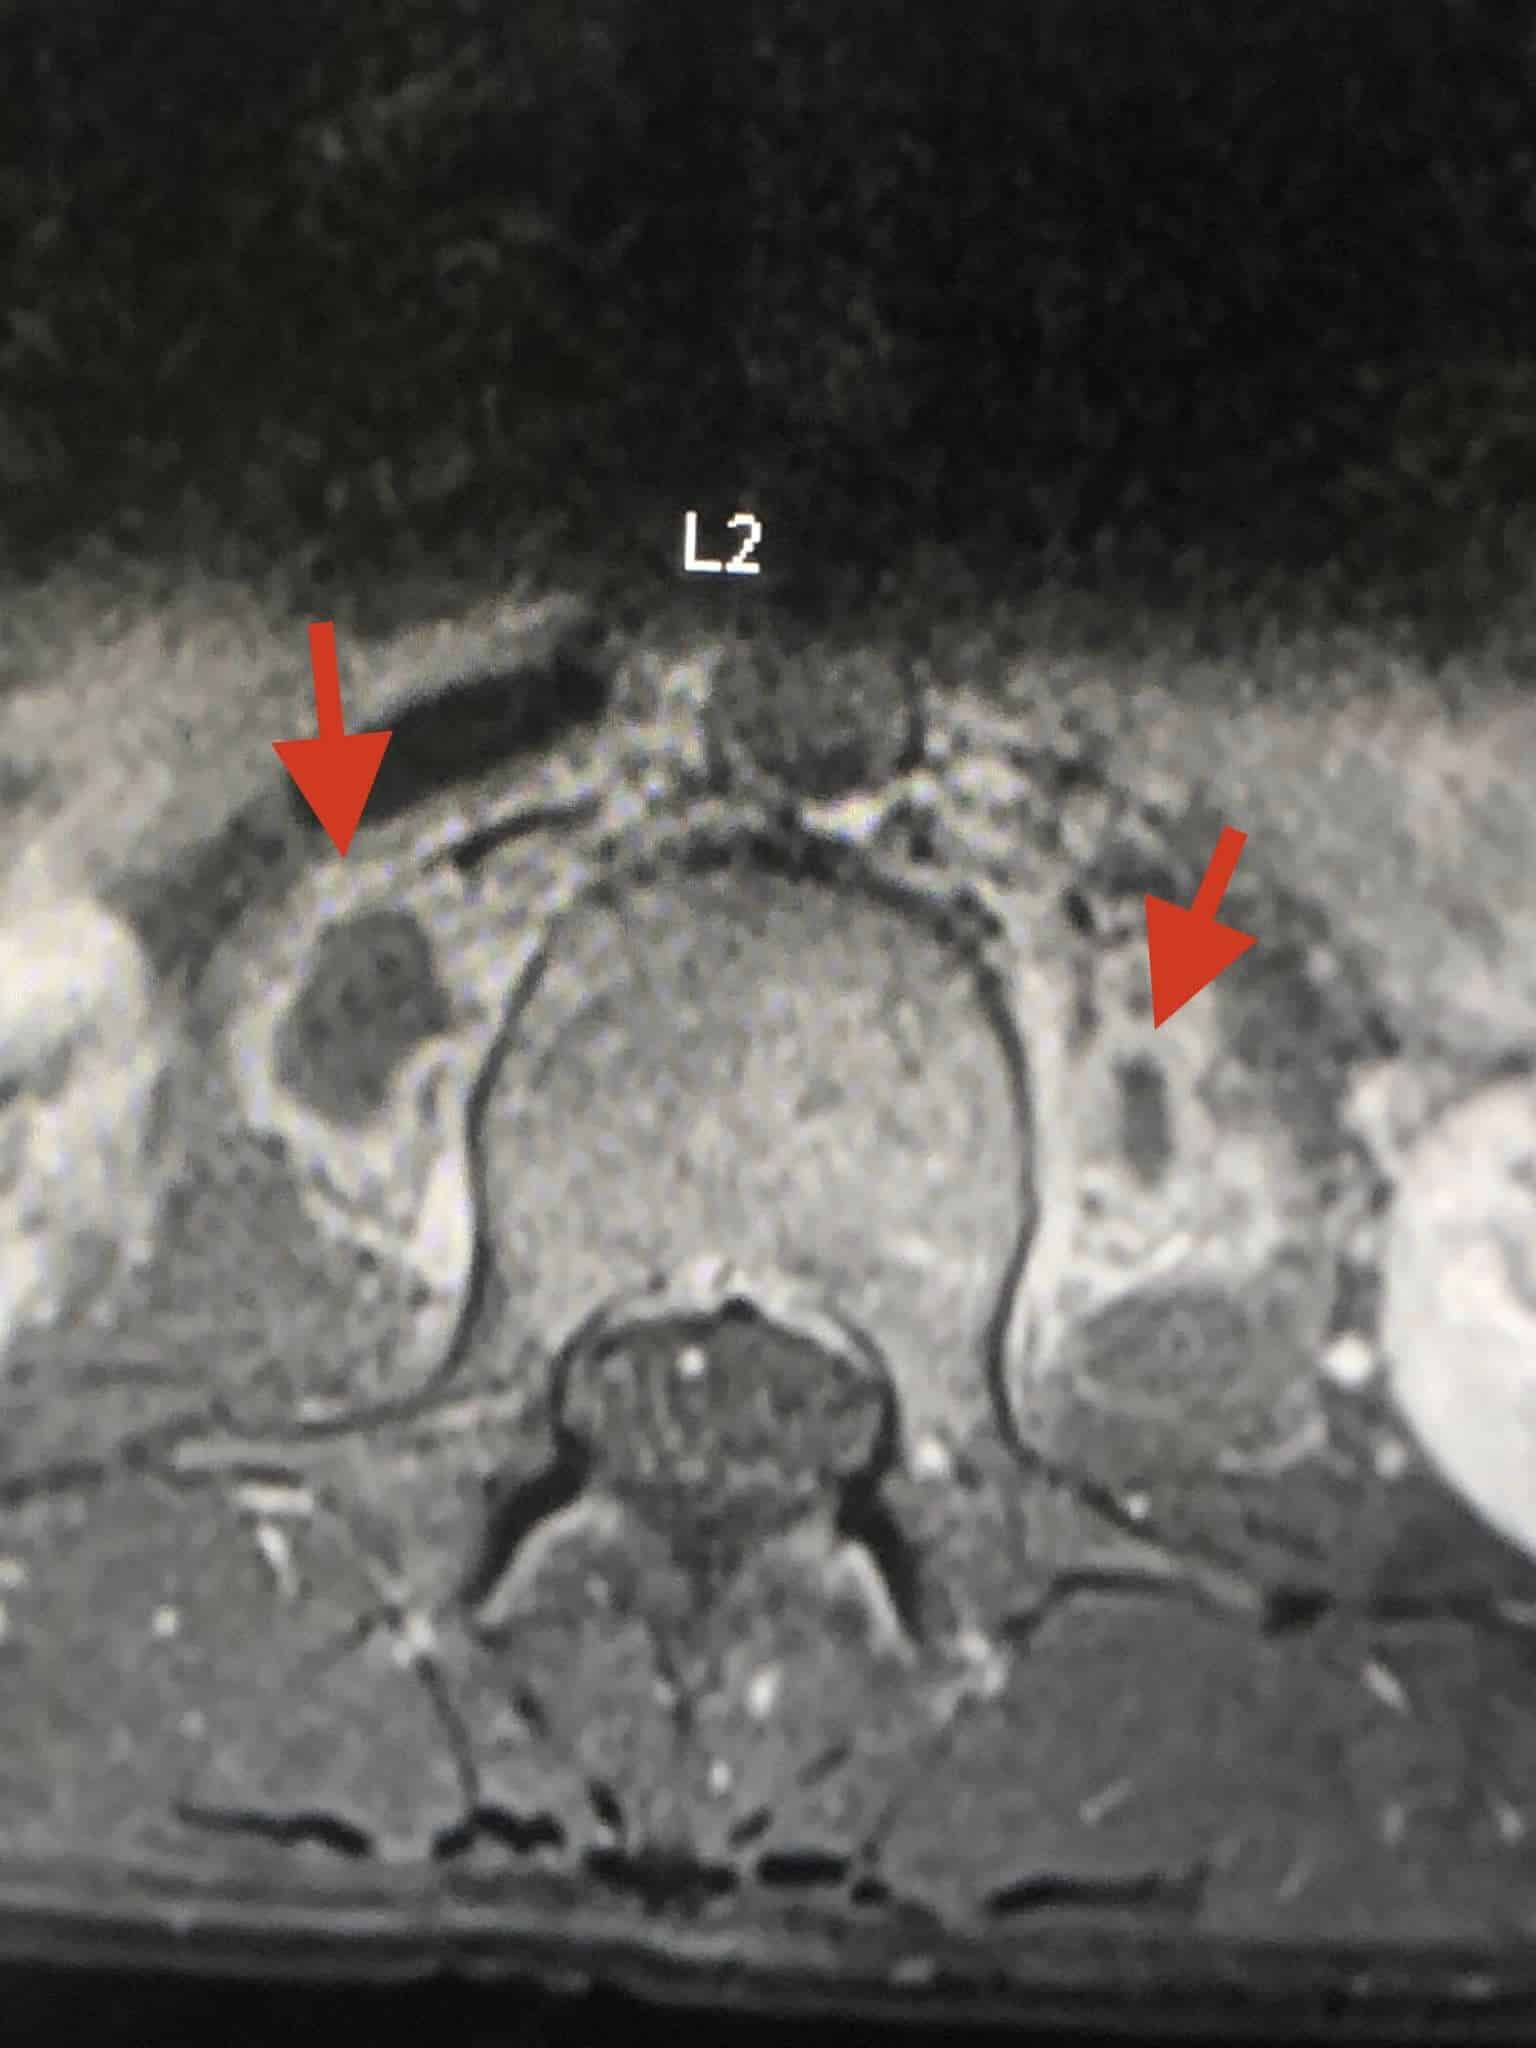

ตรวจร่างกายปกติ เจาะเลือดทุกอย่างปกติ เอกซเรย์ปอดและกระดูกสันหลังส่วนเอวปกติ ทำคลื่นแม่เหล็กไฟฟ้ากระดูกสันหลังส่วนเอว (MRI lumbar spine) ผิดปกติ สงสัยเป็นวัณโรคของกระดูกสันหลังส่วนเอว (lumbar spine) ชิ้นที่หนึ่ง และสงสัยมีการอักเสบรอบ ๆ เนื้อเยื่อกระดูกสันหลังส่วนเอวชิ้นที่ 1 และ 2 ร่วมด้วย (ดูรูป)